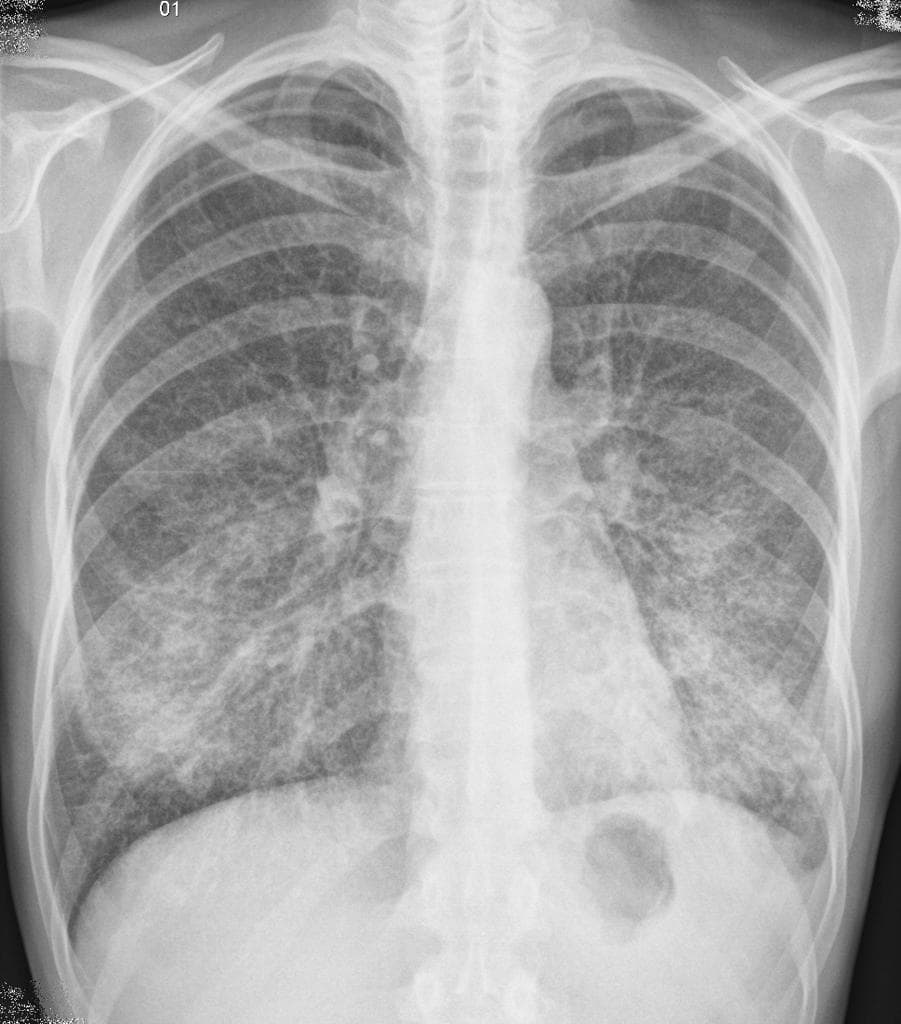

Ca bệnhViêm phổi – thùy giữa bên phải

Viêm phổi – thùy giữa bên phải

Ho và sốt.

- Đặc chắc nhu mô phổi (airspace consolidation) kèm hình ảnh phế quản khí (air bronchograms) ở vùng dưới bên phải, rõ nhất tại thùy giữa bên phải trên hình nghiêng.

- Không thấy tràn dịch màng phổi (pleural effusion).

- Tim và các cấu trúc trung thất bình thường về kích thước và hình dạng.

- Xương sườn và thành ngực không có tổn thương xương.

Viêm phổi – thùy giữa bên phải (pneumonia - right middle lobe)

Viêm phổi thùy giữa bên phải là một hình ảnh phổ biến nhưng thường bị bỏ sót trên X-quang ngực. Thùy giữa bên phải đặc biệt dễ bị ảnh hưởng bởi các quá trình tắc nghẽn và nhiễm trùng do hướng giải phẫu và lòng phế quản tương đối hẹp. Trên phim X-quang ngực trước-sau, vùng đặc chắc ở thùy này có thể mờ nhạt hoặc bị che khuất bởi bóng tim; tuy nhiên, phim nghiêng cho thấy rõ hình ảnh mờ ở vùng trước, giữa tim và cơ hoành. Dấu hiệu phế quản khí là đặc trưng của bệnh lý nhu mô phổi, cho thấy phế quản còn thông suốt trong khi các phế nang xung quanh bị lấp đầy dịch. Về lâm sàng, bệnh nhân thường có sốt, ho và đôi khi đau ngực không điển hình. Chẩn đoán phân biệt bao gồm lao phổi, áp xe phổi và ung thư phế quản phổi, đặc biệt ở bệnh nhân có yếu tố nguy cơ hoặc đáp ứng kém với kháng sinh. Việc nhận biết sớm và điều trị kịp thời bằng kháng sinh phù hợp là cần thiết để ngăn ngừa các biến chứng như xẹp phổi, tràn dịch màng phổi hoặc áp xe màng phổi.